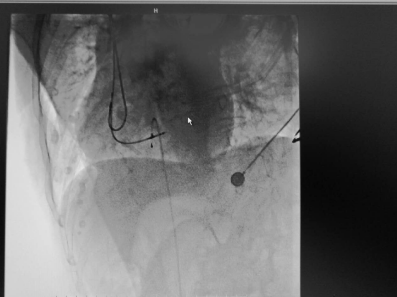

起搏器成功植入

紧急植入心脏临时起搏器——朱彬介绍,经过紧急的抢救,李婆婆虽然再次苏醒,但最根本的还是要纠正她的心动过缓问题。因为明确为病态窦房结综合征所致,朱彬立即对老人进行了临时心脏起搏器植入术,并调高起搏频率为75次/分,以纠正心动过缓所致的QTc间期延长,整个过程仅耗时25分钟。